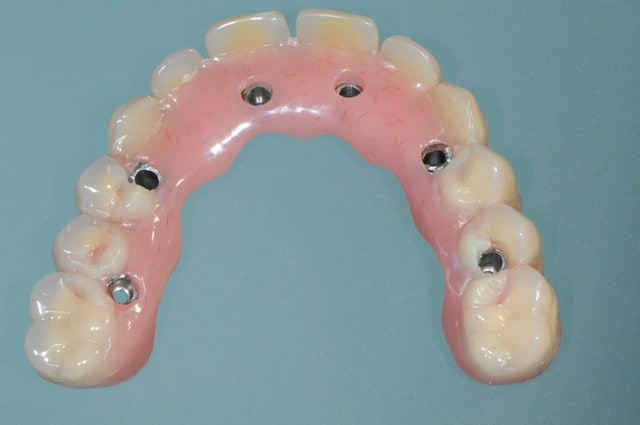

la patiente a été opérée hier et j'ai mis ses prothèses aujourd'hui.

la veille de l'intervention j'ai imprimé le model 3 D.